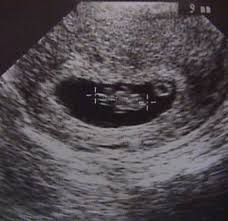

As for the 4 week ultrasound there are a few things the ultrasound can and cannot show.

It is not possible to measure fetal size at this stage. Your ultrasound may just reveal a little circle at the center which is called as a gestational sac at this stage it is not possible to see much more than the gestational sac and the sac is recognizable up until you are 4 1 2 weeks pregnant. They set me up with a tv ultrasound and after about 45 minutes they found her heartbeat. But if your doctor wants you to have one at 6 weeks they ll tell you why.

According to american pregnancy a transvaginal ultrasound may be able to detect a pregnancy as early as 4 weeks of gestation. It is not possible to determine fetal size at this stage. When it comes to the 4 week ultrasound there are a few things the ultrasound can and can not show. An ultrasound is a routine part of prenatal care at six to nine weeks.

4 weeks pregnant ultrasound. Most women never get to witness this most amazing part of their pregnancies the very beginning of their baby s lives as we can see it by ultrasound. I was 5w6d and went to the er. The ultrasounds we might do prior to that and the information those exams would reveal generally occur in four stages.

It will take at least a week longer to detect any proof of pregnancy with a transabdominal ultrasound.